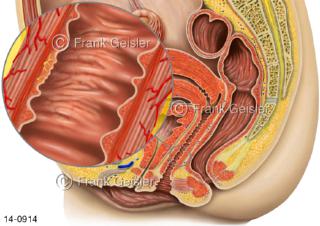

Bildergalerie Urogenitalsystem

Bilder zum Urogenitalsystem mit Urogenitalorgane, Urogenitaltrakt, zum Harn- und Geschlechtsapparat, Harnorgane und Geschlechtsorgane, Organe der Harnwege und der Fortpflanzung, Harnorgane und Geschlechtsorgane im männlichen und weiblichen Urogenitalsystem